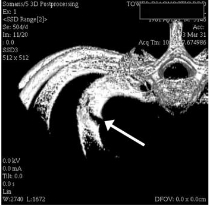

외상의 골절과는 다르게 여러개의 뼈가 부러지는 형태가 아닌 단일뼈가 부러지는 형태의

피로골절 형태의 골절이 생기는 경우가 많습니다.

진단은 물론 X-ray 나 CT, bone scan 같은 영상검사로 하게 되지만